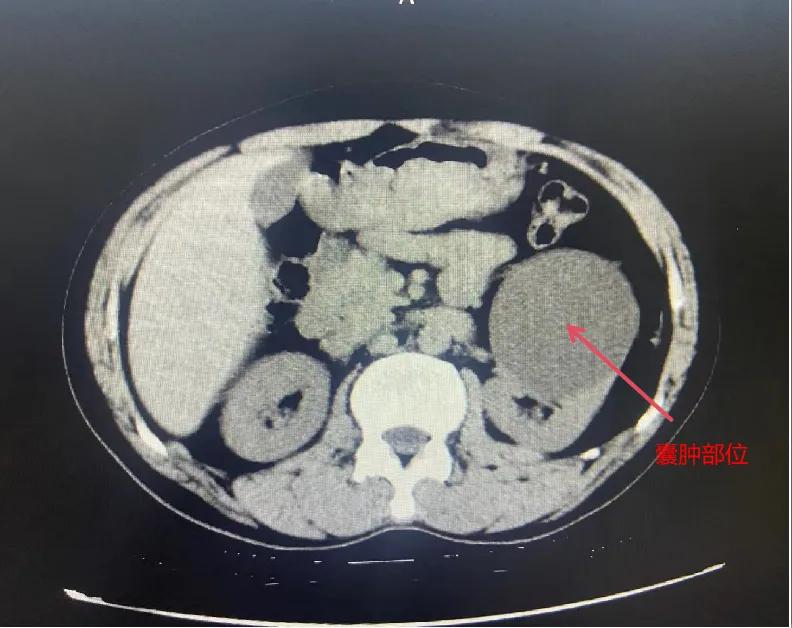

漯河市骨科醫(yī)院泌尿外科開(kāi)展后腹腔鏡下腎囊腫去頂減壓術(shù)

近日,漯河市骨科醫(yī)院(漯河醫(yī)專二附院、漯河市立醫(yī)院)連續(xù)收治2例腎囊腫患者。泌尿外科主任閆衛(wèi)甫和副主任醫(yī)師王金柱等醫(yī)師團(tuán)隊(duì)經(jīng)討論研究后,決定為患者采取后腹腔鏡下腎囊腫去頂減壓術(shù),經(jīng)過(guò)手術(shù)室、麻醉科等科室大力配合成功完成手術(shù)。

閆衛(wèi)甫表示,后腹腔鏡技術(shù)是一種微創(chuàng)外科手術(shù)方法,它通過(guò)在后腹腔(即腹膜后的空間)建立一個(gè)手術(shù)空間,利用腹腔鏡器械進(jìn)行手術(shù)操作。這種技術(shù)特別適用于泌尿系統(tǒng)等后腹腔臟器的手術(shù)。與傳統(tǒng)手術(shù)相比具有創(chuàng)傷小、恢復(fù)快、并發(fā)癥少、視野清晰等優(yōu)點(diǎn)。與前腹腔鏡相比則具有對(duì)腹腔臟器干擾較少的優(yōu)點(diǎn)。目前,后腹腔鏡手術(shù)主要用于腎囊腫去頂減壓術(shù)、腎上腺腫瘤切除、早期腎癌根治術(shù)、腎腫瘤剜除術(shù)等。

腎囊腫是一種常見(jiàn)的腎臟良性疾病,其發(fā)病率逐年增加。近年來(lái)隨著腹腔鏡技術(shù)的迅速發(fā)展,后腹腔鏡下腎囊腫去頂減壓術(shù)成為治療腎囊腫的主要方法。該手術(shù)具有創(chuàng)傷小,手術(shù)時(shí)間短,術(shù)中出血少,術(shù)后康復(fù)快,出院時(shí)間短等優(yōu)點(diǎn),并且術(shù)后復(fù)發(fā)率低,被認(rèn)為是治療腎囊腫的理想術(shù)式。(盧 闖 聶方方 劉 旭 袁錦鈺)